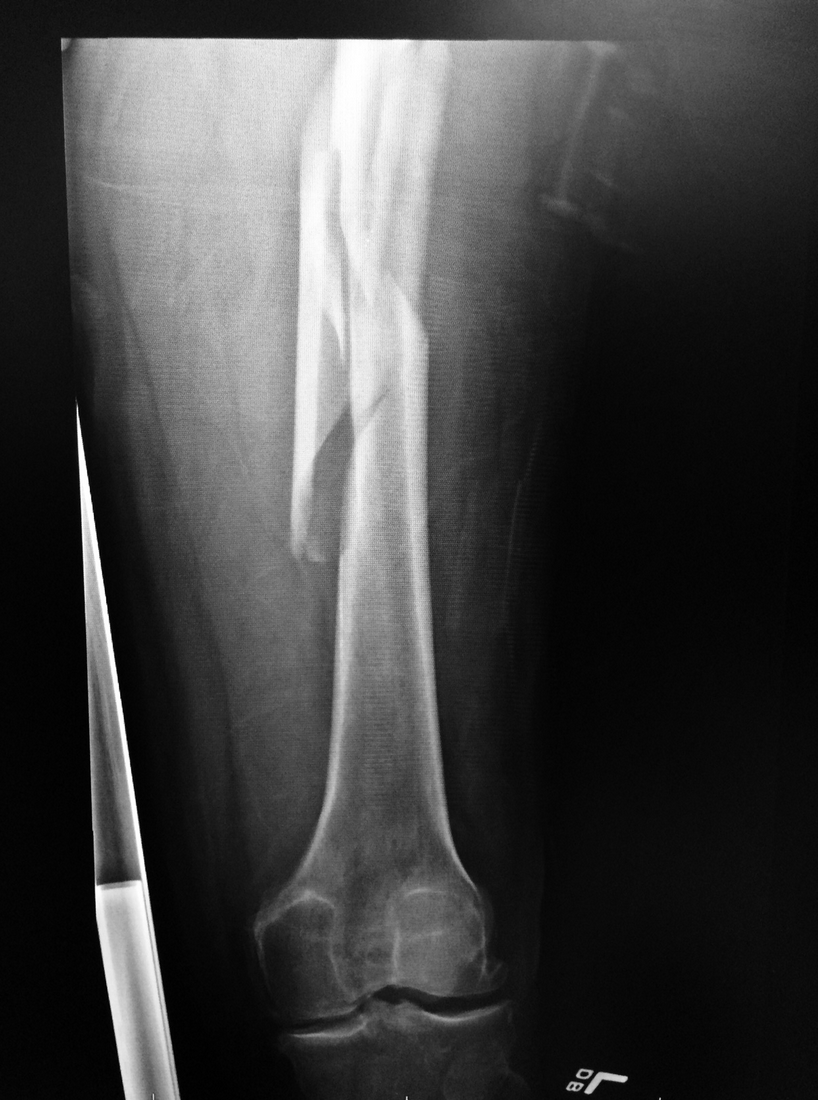

I planned a ski cut, which would lead me to a safe location, with the rest of the group in a safe area. However, halfway across the slope, I skied into some softer snow and struck a rock, which momentarily put me off balance. Before I knew it, I was headed downhill in a fast-moving stiff slab. I veered off to the right, watching my tips reach solid snow, but within a few seconds, the tails of my skis were grabbed by the rushing torrent and I was turned 360 degrees in the air. During these brief seconds, I felt my left femur spiral and fracture.

I radioed to my companions, assuring them that I was not buried but that I did have a fractured femur. Next, I removed my pack, dug out my leg, and placed it gently on the backpack. The adrenaline was still rushing through my body; I felt very little pain as I tried to adjust my leg into a more comfortable position. The thought that I would see my family and friends was comforting, but first, I needed to deal with my femur.